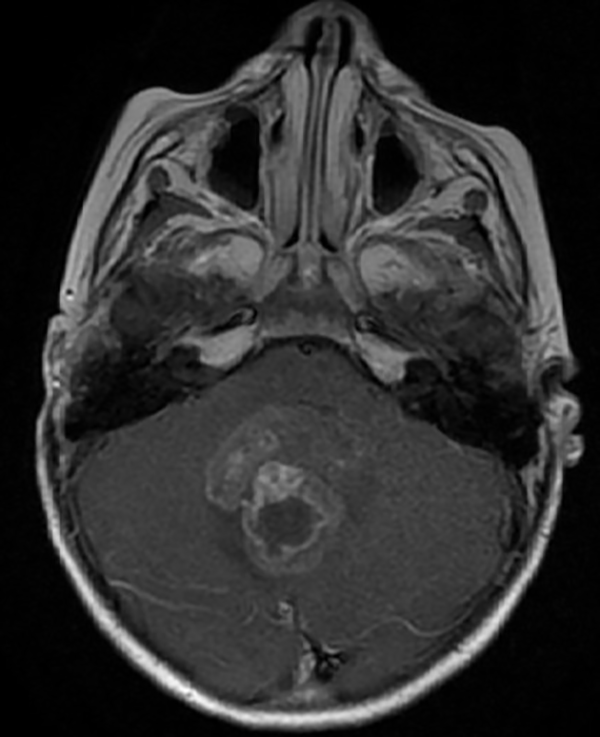

En resonancia magnética (RM) de cerebro se observa tumoración heterogénea sólida o sólido-quística con áreas de hemorragia, quistes y calcificaciones, que capta contraste en forma variable. (Fig. 1, 2, 3, 4). El patrón en espectroscopía se caracteriza por presentar pico de Colina (Cho) y descenso de N-Acetilaspartato (NAA).

Fig 1: RM corte axial, secuencia T1 con contraste. Se observa neoformación medial, solido-quística, heterogénea de bordes irregulares en la topografía del VI ventrículo que ocupa la totalidad del mismo, que realza en forma heterogénea tras la administración del contraste.